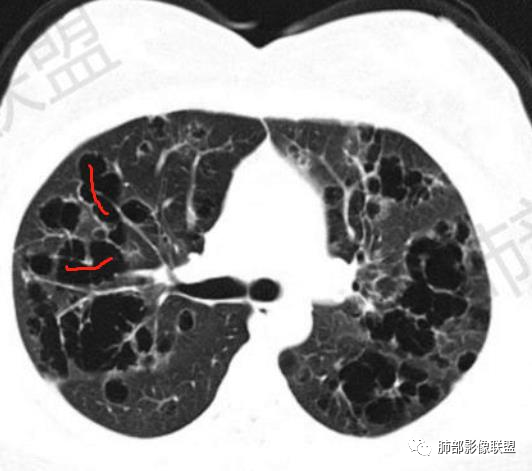

晨读:双肺多发大小不等囊腔影,部分囊有融合,形态不规则,部分壁偏薄,部分囊壁偏厚,囊壁可见结节?血管?右肺上叶及左肺下叶可见条状高密度影,双侧胸膜结节样增厚,临床年轻女性,考虑LAM,鉴别LIP

晨读,青年女性,双肺及胸膜下多发大小不等囊腔,大部分呈薄壁,部分囊壁略厚,边缘毛糙,部分囊腔有融合,双肺内散在条状高密度影,考虑LAM

影像:双肺散在囊性病变,不规则,壁厚,部分见结节

晨读:女,31,间断咳嗽、咳痰9月。卵巢交界性囊腺瘤术后。胸部CT:双肺多发大小不等薄壁囊腔影,部分融合,形态不规则,个别囊壁偏厚。右肺上叶及左肺下叶纤维索条影。左下叶不规则囊腔影,壁不均匀增厚,周围不规则实性成分加GGO,放射性毛刺,胸膜牵拉。考虑:囊腔型Ca?转移?鉴别PLCH,Lam,LIp,BHD,CF,CPAM等,听大咖解析。

胸部CT:两肺多发囊腔,中上肺受累为主,囊腔形态不规则(囊有点丑),分叶状,囊壁厚薄不均,大部分囊壁薄。尚有一些结节影。

晨读病例囊长得不漂亮,也没有呼吸困难等症状,不怎么支持LAM。

晨读囊不规则,分叶,存在PLCH可能,但为不吸烟女性,可能性下降。